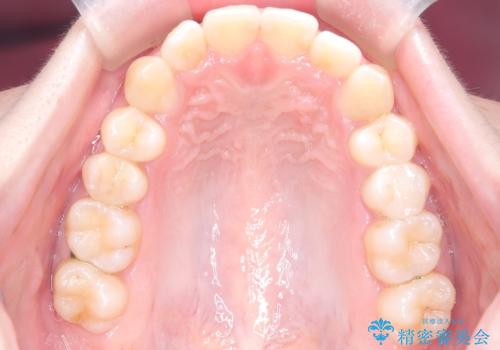

- 右上の前歯(2番)が下の歯より内側に入っている反対咬合を主訴にご来院されました。精密な検査の結果、この反対咬合を解消するためには、右上の歯列に前歯を出すためのスペースを確保する必要があると判明しました。患者様のご希望に合わせ、透明で目立たないインビザライン(マウスピース矯正)による治療計画を立案。奥歯全体を奥へ動かす遠心移動でスペースを作り、反対咬合を解消することを目指します。

今回の矯正治療では、透明なマウスピース型の装置インビザラインを使用しました。治療は、緻密なデジタル計画に基づき、奥歯から順に歯列全体を後方へ移動させる遠心移動を実施し、前歯を前に出すためのスペースを確保しました。このスペースを利用して、内側に入り込んでいた右上2番をスムーズに前方に誘導し、正常な咬み合わせへと改善。目立たないインビザラインで、機能的な咬み合わせと美しい前歯の並びを獲得していただけました。